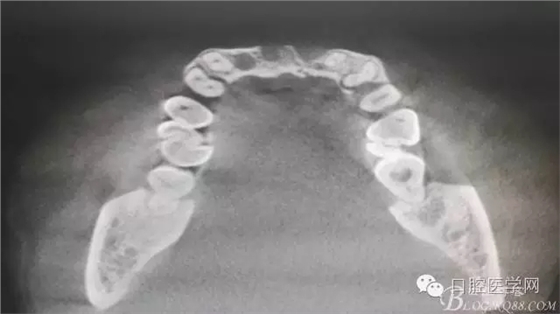

為他院轉(zhuǎn)診患者。男,無吸煙史,前牙因齲壞治療后,外力折斷導(dǎo)致拔除?,F(xiàn)拔除該牙后兩個多月。 左上區(qū)域骨寬度不足,計劃植入種植體同期GBR。

植入種植體左側(cè)3510,右側(cè)4010,植骨Bioss,蓋膜Cytoplast。骨膜減張垂直褥式縫合加間斷縫合。

遺憾沒有保留術(shù)前口內(nèi)照片,只有術(shù)后的。